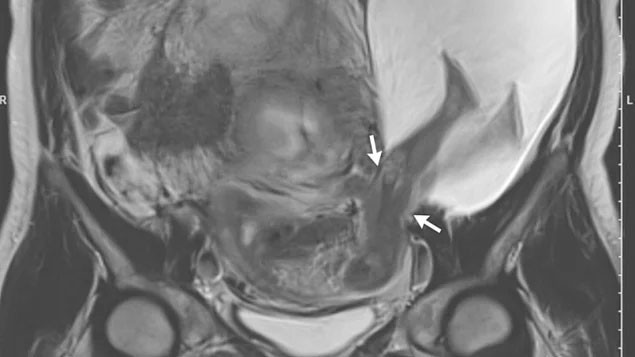

Doktorlar, rutin testleri yürüttükleri sırada, annenin sol rahim duvarında 2.5 santimetrelik bir yırtık olduğunu ve bebeğin bacaklarının bu boşluktan dışarı çıktığını gördüler. Rahim ve amniyotik sıvı, bebeği dışarıdan gelecek darbelere karşı korumakla görevlidir. Bu sebeple yaşanan olay, annenin ve bebeğin hayatını tehdit edebilecek ciddiyetteydi.

Anne karnındaki bebek tekmeleriyle rahim duvarını yırttı! - Resim: 4

Rahim duvarının bir noktadan yırtılması, anne rahminin tamamının zarar görmesine yol açabilirdi. Öte yandan “placenta accreta” adı verilen ve hem annenin hem de bebeğin yaşamını tehdit eden durum ortaya çıkabilir, doğumdan sonra aşırı kanamaya yol açabilirdi. Ayrıca anne gerekirse rahim ameliyatı olabilir, bu durumda erken doğum yapması gerekebilirdi.